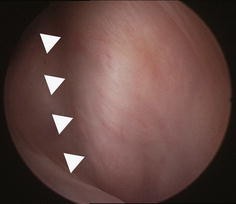

Before MPFL reconstruction, the patella in all patients was shifted laterally throughout the entire range of knee motion. Immediately after MPFL reconstruction, patellar malalignment was corrected in all cases. On second-look arthroscopy, two different patellar tracking patterns were observed. In 9 knees, the patella was located on the center of the femoral groove throughout the range of motion. Meanwhile, in the remaining 16 knees, the patella was shifted laterally at knee extension and migrated to the center of femoral groove with increased knee flexion. No significant deteriorations in chondral status were seen on second-look arthroscopy.